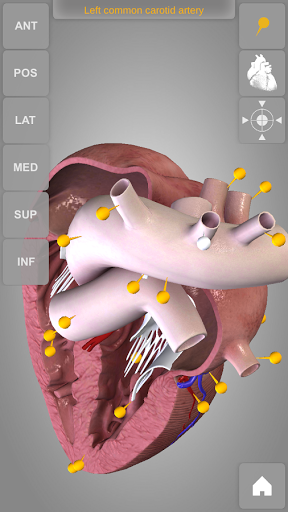

The human heart anatomical 3D model is revolvable in any direction giving a 360° view of the object.

User can choose external view or section view. Moreover, the names of specific anatomical areas can be shown touching the related pins (available in the full version only).